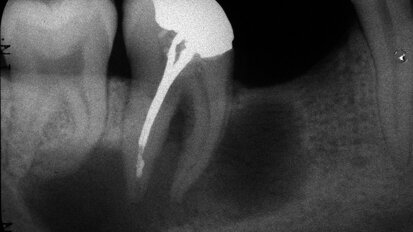

Évaluation complète d’un traitement de canal radiculaire supérieur

J'ai récemment reçu un e-mail, d'un dentiste généraliste, avec l'image de la dent 27 (image 1). Le mail : "j'ai une ...